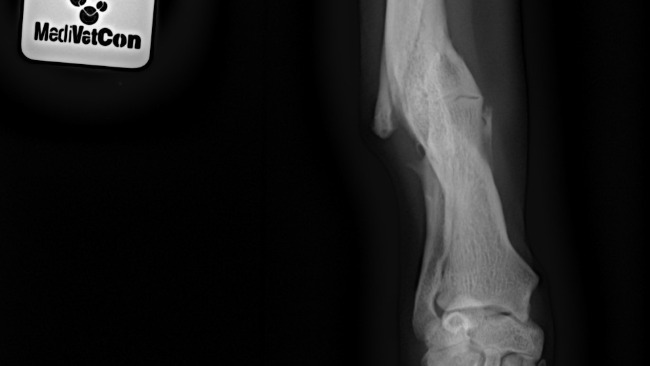

W wyniku wypadku doznała złamania przedniej łapki i przez wiele tygodni cierpiała w bólu. Dopiero kiedy udało nam się ją zabezpieczyć przy pomocy klatki-łapki, mogliśmy odetchnąć z ulgą. Kolejne psie życie zostało uratowane – Tysia nie zginęła pod kołami samochodu.

Na początku lutego Tysia była na konsultacji ortopedycznej, podczas której wykonano zdjęcie RTG. Początkowo rokowania co do operacji nie były pomyślne. Jednak we wtorek została zabrana na kolejną konsultację i pan doktor dał zielone światło! 😍